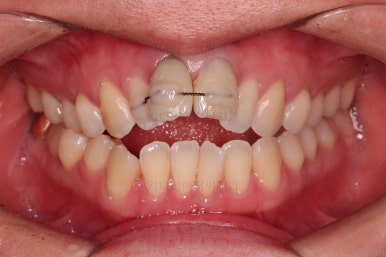

1. 초진

부산개방교합 키다리아저씨치과에 처음 내원 시 입안의 모습입니다.

전반적으로 치열이 삐뚤고요.

앞니쪽이 다물어지지 않는 개방교합(오픈바이트, open bite) 을 보였습니다.

어금니 맞물림을 보면 앵글씨 2급 부정교합 양상이어서 위아랫니가 모두 1대1로 부딪히고 있는 상태였습니다.

2급 부정교합인 분들의 특징이 앞니가 튀어 나와 있어서 돌출입 양상을 보이는 경우가 많습니다.

개방교합이어서 윗니 앞니가 들려 올라가서 심미적으로 좋지 못한 상황이었고요.